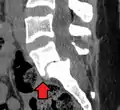

- Anterolisthesis L5/S1. Blue arrow normal pars interarticularis. Red arrow is a break in pars interarticularis.

Computed Tomography (CT)

Computed tomography can be helpful in evaluating bony vertebral abnormalities, such as fractures.[33] This can be helpful in determining if the fracture is a new, old, and/or progressing fracture.[33] CT use in spondylolisthesis evaluation is controversial due to high radiation exposure.[34]